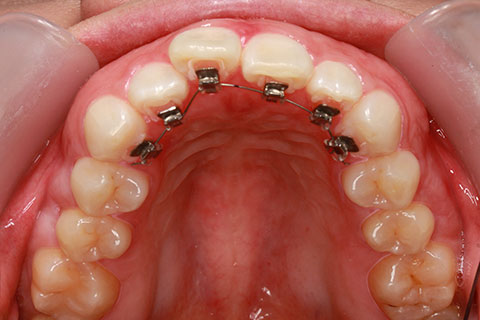

ハーフリンガル矯正3:上の歯のみ舌側矯正で治療(矯正期間24ヶ月)

治療前

治療中(開始直後)

治療中(開始半年後)

治療後

- 年齢・性別

- 25歳女性

- 治療期間

- 2年0ヶ月

- 抜歯

- 上下4番抜歯

- 治療費

- 110万円

- 治療内容

- 施術の副作用(リスク)

- 表側矯正と比較して、力学的な操作性が複雑なため、ボーイングエフェクトを起こしやすい。